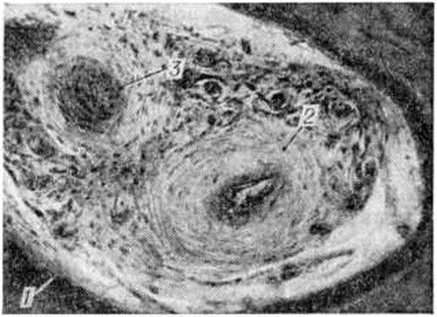

Рис. 2.

Микропрепарат костной ткани челюсти при пародонтозе: 1 — костные пластинки; 2 — артерия с утолщёнными стенками и суженным просветом; 3 — облитерация просвета сосуда; окраска гематоксилин-эозином; × 200.

Пародонтоз может протекать с преимущественным развитием в околозубных тканях дистрофических изменений с характерной атрофией костных трабекул губчатого вещества, выраженным очаговым остеосклерозом, чередующимся с очаговым остеопорозом (рисунок 1). Патологический изменения в костной ткани сочетаются с выраженными изменениями её кровеносных сосудов: гиперплазией внутренней оболочки, склерозом и гиалинозом средней оболочки, резким сужением или полной облитерацией просвета сосудов (рисунок 2). В соединительнотканной основе десны также отмечаются выраженные изменения сосудов, проявляющиеся пролиферацией эндотелия, образованием пристеночных тромбов, иногда развитием картины васкулита; на этом фоне довольно часто наблюдается набухание коллагеновых волокон, их фрагментация и даже лизис. В целом состояние десны характеризуется развитием в ней вялотекущего воспалительного процесса, в соединительнотканной строме десны обнаруживают инфильтраты из плазматических и лимфоидных клеток, локализующиеся преимущественно в области десневой борозды.